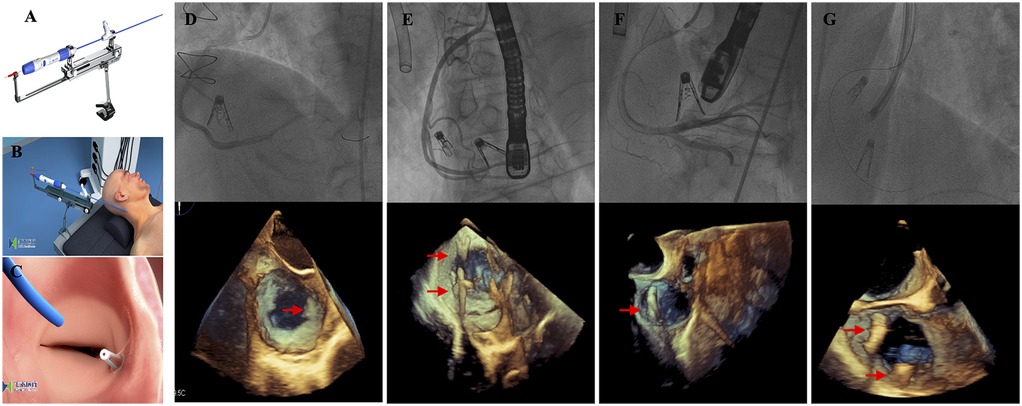

On the basis of echocardiography and CT measurements, a clip of K-Clip™ was selected for implantation. After signing informed consent, the procedure was carried out. The interventional procedure was performed under general anaesthesia, angiographic and TEE guidance (Figures 1A–C). Step 1; Trans-vascular access: After right jugular vein puncture, lead K-Clip ™ sheath introducer access RA throughout SVC, in addition, a guide catheter needs to be placed in the right coronary artery via femoral access because of the close proximity of the right coronary artery to the posterior portion of the tricuspid annulus; Step 2; Sheath Position: Figure out the tricuspid annulus guided by TEE and position the sheath introducer; Step 3; Anchor Deployment: Under the guidance of TTE and TEE, the anchor of K-Clip ™ reaches the midpoint of the posterior tricuspid annulus and tap the anchor screw into annulus; Step 4; Clamping Annulus Tissue: Under the guidance of TTE and TEE, clamp the tissue to fold the tricuspid annulus and then close the Clip arms slowly; Step 5; Sandwich Formed: Form the stable “Anchor-tissue-clamp arm” sandwich structure; Step 6; Release: Release the sandwich-like K-Clip ™ and withdraw the delivery system. Right jugular vein access was closed using a ProGlide closure system (Abbott Vascular) while manual pressure was held for haemostasis of the left femoral artery.

Figure 1. Procedural technique and results. (A) The K-Clip™ system; (B) The procedure was performed under general anesthesia and transjugular access; (C) After the clip released, the tricuspid annulus length was reduced; (D–G) The K-Clip™ device was successfully implanted in all four patients—2 patients with 2 clips each and 2 patients with 1 clip each, and 3D transesophageal echocardiography displayed the position of the clips (red arrow).

The key procedural characteristics of our study population are summarized in Table 2. In all patients, 1 clip or 2 clips each were successfully applied and the delivery system was retrieved as intended (Figures 1D–G). Procedural success was achieved in 4/4 (100%) patients, and there was no conversion to surgery. The mean operation and fluoroscopy times were 93.6 ± 23.4 min and 30.4 ± 15.7 min, respectively. In general, TR severity was effectively reduced by at least 1 grade in all 4 patients (100.00%). One patient still exhibited severe TR after the procedure. No procedural-related complications were observed. No other major adverse cardiac or cerebrovascular events were reported in our study population.